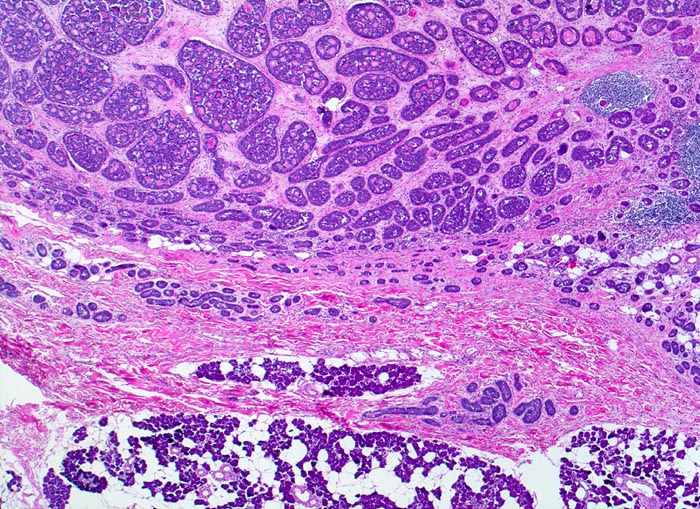

Adenoidzystische Karzinome zeigen drei Wachstumsmuster (in abnehmender Reihenfolge): kribriform, tubulär und solide. Die Hohlräume in den kribriformen Arealen entsprechen keinen echten Drüsenlumina, sondern sind Bestandteil des Tumorstromas. Sie enthalten PAS positives Sekret oder hyaline Substanzen. Die strangförmigen Tubuli begleitet von hyalinem Stroma. Typischerweise (allerdings nicht im vorliegenden Präparat) kann eine Perineuralscheideninvasion nachgewiesen werden. Kleine Tumoren können scharf begrenzt sein, grössere Tumoren wachsen infiltrativ.

• Reste einer rein serösen Speicheldrüse (rechts).

• Unscharf begrenzter, aus kribriformen, tubulären und soliden Zellformationen aufgebauter infiltrativ wachsender Tumor.

• Mikrozystische Hohlräume in den kribriformen Tumorarealen enthalten eosinophiles hyalines Material.

• Tubuli mit zentralem Lumen werden ausgekleidet von einer inneren helleren Epithelschicht und einer äusseren dunkleren Myoepithelschicht.

• Basaloide kleine Tumorzellen mit wenig Zytoplasma.